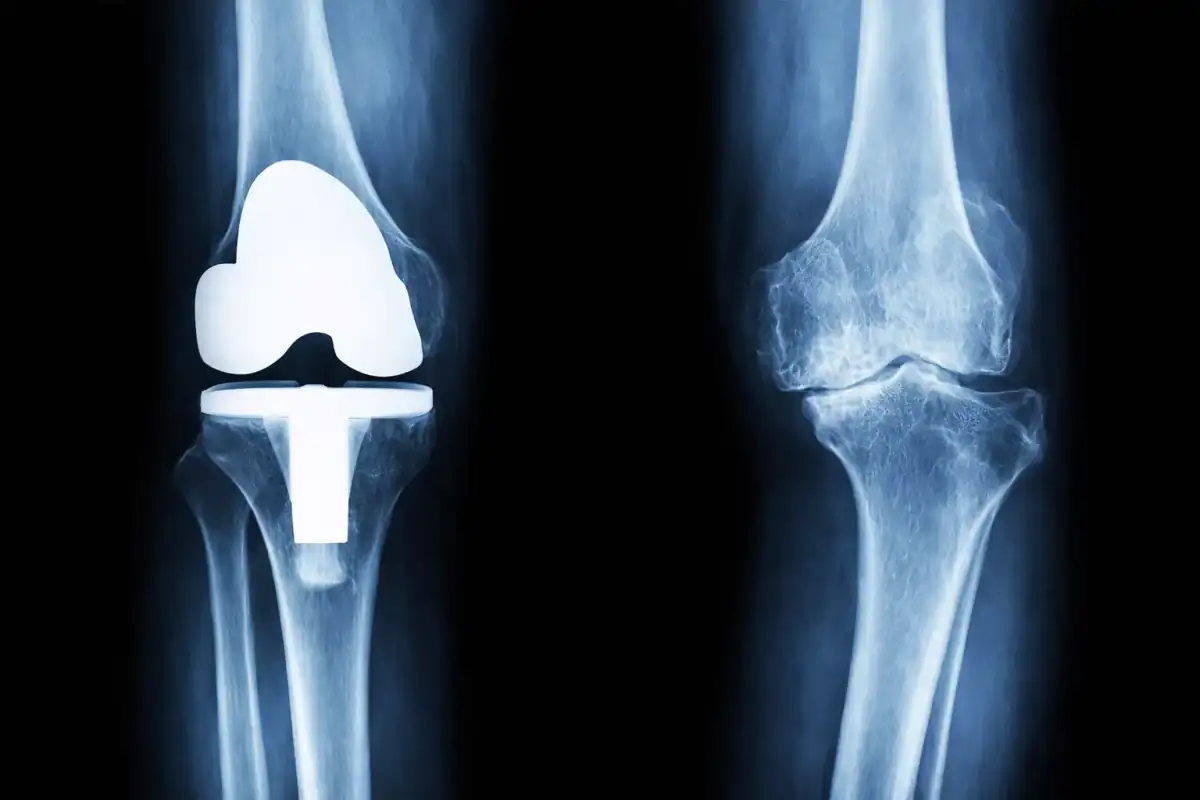

Protesi di ginocchio con tecnologie digitali e sistemi assistiti da Intelligenza Artificiale

Nel trattamento di queste condizioni, quando indicato, la protesi di ginocchio può rappresentare una soluzione chirurgica per ridurre il dolore e migliorare la funzionalità articolare.